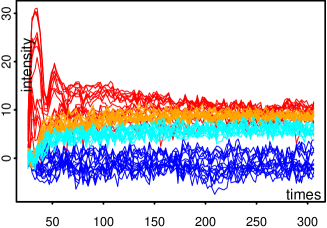

The two real DCE-MR image sequences have been fully segmented into homogeneous regions that are highly consistent with anatomical structures as shown in Figure 13. The smaller is, the more details in anatomical structures can be observed in image sequence. This is highlighted (see Fig. 14) in the ROIs defined by the squares that contain the manually segmented ROIs, shown in black on Figure 13. The corresponding estimated TCs inside each cluster within the ROI together with their corresponding size are shown in Figure 15. By segmenting the full DCE sequence, these estimated TCs are obtained by averaging TCs which do not necessarily belong to the ROI but do belong to the same homogeneous cluster. As a benefit, the SNR observed for these estimated TCs is strongly improved, providing a real opportunity for further analysis and comparisons. From these figures, one can clearly understand the advantages of DCE-HiSET. It is indeed providing a piecewise constant representation of the DCE image sequence in functionally homogeneous regions, where controls the size of the pieces and the functional discrepancy between them.

Patient 1

Patient 2